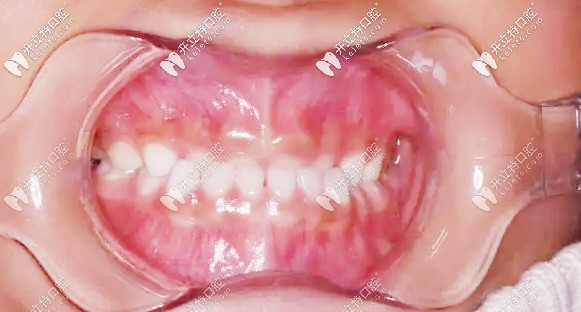

我孩子現(xiàn)在3歲零4個(gè)月,檢查結(jié)果:現(xiàn)在是乳牙期,出現(xiàn)乳牙反合,也就是地包天,醫(yī)生建議做矯正,作為新手寶媽,當(dāng)時(shí)的我是崩潰的~

矯正前牙齒地包天